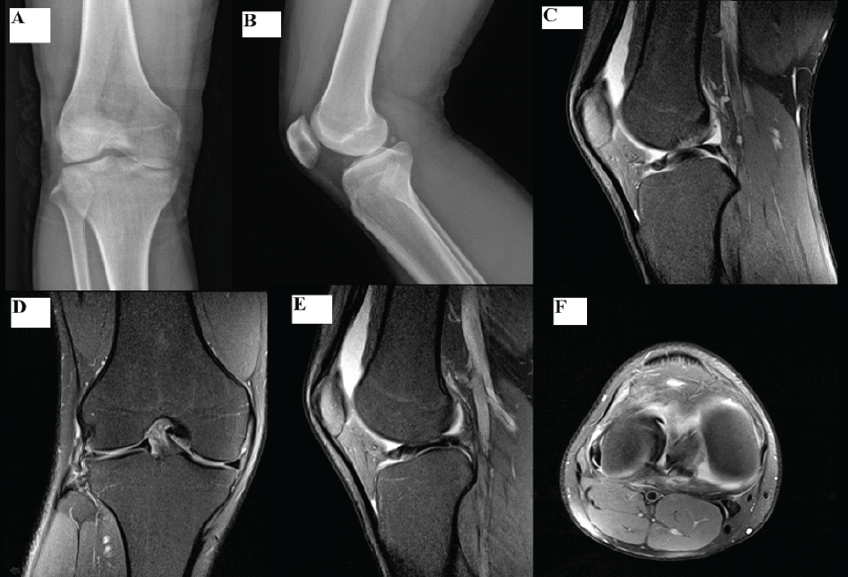

A 20-year-old male football player presented to the emergency department with acute right knee flexion deformity and locking after a twisting injury during play. Clinical examination revealed lateral joint-line tenderness, limited flexion, and inability to extend the knee fully. Lachman test and pivot shift tests were negative. Plain radiographs showed no fracture or dislocation. Magnetic resonance imaging (MRI) demonstrated a displaced bucket-handle tear of a discoid LM, with the classic double-posterior cruciate ligament sign and minimal chondral change (Fig. 1c-e).

Figure 1: Pre-operative imaging of the right knee. (a) Anteroposterior radiograph showing flexion deformity due to meniscal locking. (b) Lateral radiograph of the knee. (c) Sagittal T2-weighted magnetic resonance imaging (MRI) showing the “double posterior cruciate ligament” sign (d) Coronal T2-weighted MRI showing a flipped meniscal fragment within the intercondylar notch. (e) Axial MRI showing a displaced meniscal fragment within the intercondylar notch, producing a characteristic double-layer (split-meniscus) appearance (f).